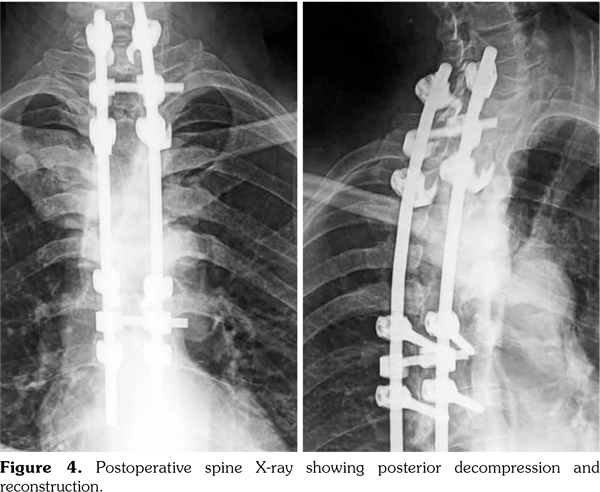

Thus, the diagnosis of SAPHO syndrome was established. Despite the use of nonsteroidal antiinflammatory drug, the disease remained active as attested by Bath Ankylosing Spondylitis Disease Activity Index at 6.7 at three-month follow-up. Then, the patient was lost to follow-up. One year later, he presented with hypesthesia and muscle weakness of his lower limb associated with kyphotic deformity and sphincter symptoms. He was unable to walk. Magnetic resonance imaging showed a vertebral collapse associated with spinal cord compression at T5 (Figure 3). Surgical treatment based on decompression and reconstruction with screw fixation was performed (Figure 4). The histopathology of the specimen obtained surgically showed nonspecific osteomyelitis with an infiltration of inflammatory cells and abnormal fibrous hypertrophy among the trabecular bone. One year later, etanercept was administered at a dose of 50mg weekly, leading to complete resolution of articular manifestations. Clinical remission was obtained under etanercept (Bath Ankylosing Spondylitis Disease Activity Index at 2.1). After two years of follow-up, patient’s paralysis improved by surgery, and he was progressively able to walk.

The spinal lesions in SAPHO syndrome usually have a good prognosis and rarely cause neurological deterioration.(5) In fact, they generally have an insidious onset and repeated recurrence and remission. In SAPHO syndrome, destructive lesions progress associated with marginal sclerosis explaining why destructive spondylodiscitis progresses slowly. However, if the speed of destruction by inflammation is faster than that of sclerotic reaction, the spinal structure would break.(8) We described herein a case of SAPHO syndrome complicated by severe destruction and kyphotic deformity leading to paralysis. To our knowledge, there are only seven cases of SAPHO syndrome with neurological deficit summarized in Table 1.(9-14) Surgery was performed leading to improved neurological signs.